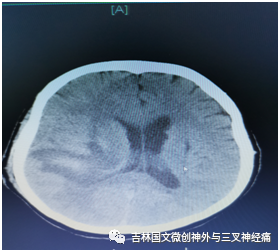

患者郝某,是一名糖尿病患者,既往有兩次腦出血病史,本次因突發(fā)意識不清于2020年11月12日急診來我院救治,經(jīng)檢查為:右側(cè)大量腦出血破入腦室,入院時患者已處于昏迷狀態(tài),呼吸、咳痰費(fèi)力,左側(cè)巴花斯基征陽性??紤]病人為第三次腦出血,可能存在血管畸形等血管病變情況,入院后立即安排頭部CTA檢查,結(jié)果回報未見明顯動脈瘤及血管畸形等情況,考慮為高血壓、動脈硬化引起腦出血,為了減少副損傷,經(jīng)與家屬溝通,我們采取了血腫腔置管液化引流手術(shù)治療。

術(shù)后引流良好,意識逐漸轉(zhuǎn)清,根據(jù)復(fù)查頭部CT結(jié)果拔出血腫腔引流,因腦室內(nèi)仍有大量血液,防止腦積水的發(fā)生,術(shù)后又采取了腰大池引流治療,徹底把腦室內(nèi)積血引流干凈;病人盡管意識恢復(fù),但咳痰能力差,為了保障呼吸道通暢,給予氣管切開促進(jìn)排痰,病情逐漸好轉(zhuǎn)。